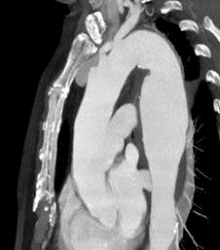

Mit einer über die Leistenregion minimal invasiv eingebrachten Stentgraft – Prothese versorgtes Aneurysma der Hauptschlagader im Brustbereich

Dabei handelt es sich zumeist um modulare Prothesensysteme. Hierdurch wird der Gefäßstrom durch die Prothese geleitet und somit das Aneurysma ausgeschaltet.

Minimalinvasive Eingriffe haben den Vorteil einer erniedrigten peri/postoperativen Mortalität, einer deutlich verkürzten Liegedauer und benötigen so gut wie keine rehabilitierenden Maßnahmen, allerdings müssen die Aortenprothesen jährlich mittels CT-Angiographie kontrolliert werden um etwaige Komplikationen (weiteres Aneurysmawachstum, Materialdefekte) frühzeitig zu erkennen und in weiterer Folge auch beheben zu können.